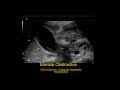

ICTERICIA OBSTRUCTIVA. Colangiocarcinoma. Dilatación de vías biliares. Hidrocolecisto. Dilatación del conducto pancreático principal. Ascitis. Pequeñas lesiones hepáticas de predominio periférico. Engrosamiento difuso de las paredes gástricas.camera iphone 8 plus apk Ictericia obstructiva | |